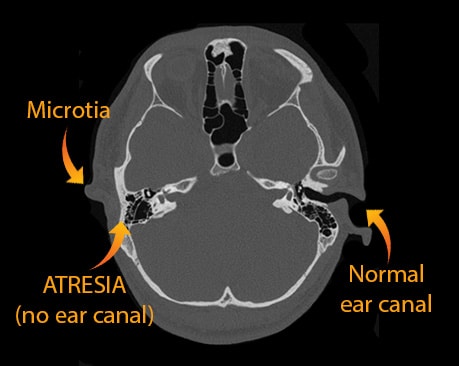

Most patients born with microtia also have "aural atresia" (lack of an ear canal). Luckily, these children usually have a normal inner ear and hearing nerve (cochlea), which means they are not deaf. Instead they have conductive hearing loss which can be treated by Dr. Bonilla as well.

Is a child with microtia deaf? In almost all cases, the answer is no. Why? During in-utero development the outer ear and middle ear form at about the same time. When there is a severe congenital malformation of the outer ear, such as a microtia, then there is usually a malformation of the middle ear as well. Most of the time, the middle ear malformation consists of fused or malformed middle ear bones, a smaller middle ear cavity and an abnormal course of the facial nerve.

In conclusion, a child with a microtia will usually have normal sensorineural hearing and moderate to severe conductive hearing loss. All this means is that the child’s inner ear is normal (normal sensorineural status), but because there is no ear canal, there is no way for sound to “conduct” to the inner ear via the ear canal. As a result, there will be conductive hearing loss.